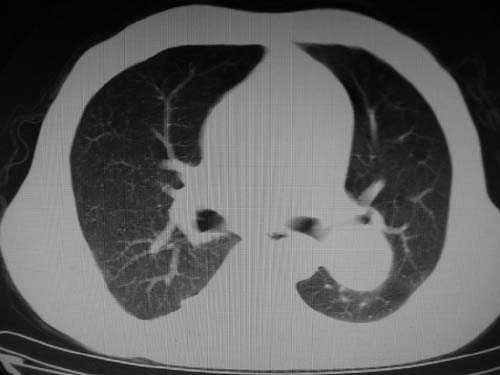

标题: CT17069:M80Y,请战友们看看像啥 [打印本页]

标题: CT17069:M80Y,请战友们看看像啥

男,80岁

肺a高压征[左肺a狭窄?];肺,胸膜tb

右肺上叶结核;左肺门占位?建议增强扫描.

左下肺静脉扩张,原因?建议cta

左肺动脉异常增粗,建议增强。

1)考虑肺动脉狭窄。2)右肺上叶继发性肺结核。3)右侧胸膜增厚、钙化,左侧胸膜反应。

肺动脉瘤。建议先行ct增强扫描

左肺动脉异常增粗,考虑肺动脉狭窄可能。

右肺上叶继发性肺结核。

右侧胸膜增厚、钙化,左侧胸膜反应。

左肺动脉异常增粗,建议ct增强,排除肺门肿瘤

右侧胸膜增厚、钙化,左侧胸膜反应

双肺陈旧性病变,左肺动脉高压.

1)考虑左肺动脉瘤可能性大,建议增强。2)右肺上叶继发性肺结核。3)右侧胸膜增厚、钙化,左侧胸膜反应。

肺动脉段突出,左右肺门不等大,左肺门明显增大,肺动脉干及左肺动脉明显增宽,考虑先天性肺动脉狭窄瓣膜狭窄型。

)考虑肺动脉扩张,右心室增大,主动脉弓段正常位弓后段明显变小(不会是动脉导客未闭吧,不知患者有何症状病史)0。2)右肺上叶继发性肺结核。3)右侧胸膜增厚、钙化,左侧胸膜反应。

右肺上叶尖段结核;左肺下叶占位?建议增强扫描。右侧胸膜增厚;右肺局限性肺气肿。

结合患者年龄,不除外左下肺扩张性动脉瘤,建议胸透是否有扩张性博动,以便确诊。

肺动脉高压,左肺动脉瘤样扩张。

肺a高压